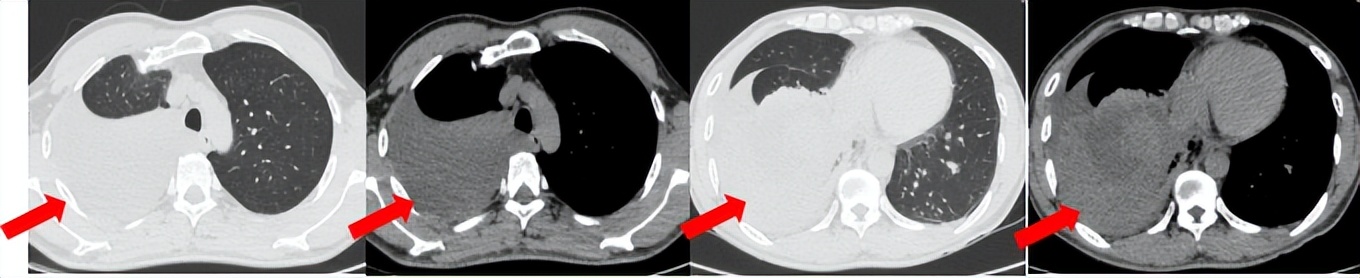

55岁男性,无吸烟史,有饮酒嗜好。2024年11月常规体检胸CT:左肺上叶占位性病变,大小约2.7×2.4cm,恶性可能大;左肺、左侧叶间胸膜及胸膜下多发微小结节,转移待除外。左侧胸腔积液,部分骨质改变。2024年12月初肺穿刺活检,病理:(肺)腺癌。NGS基因检测:CCDC6-RET(exon1-exon12)融合突变阳性(丰度:13.21%)。PD-L1表达阳性(TPS=35%,CPS=45)。

治疗经过:2025.01开始口服普拉替尼(400mg,qd)。2025.03复查胸CT:左肺上叶、右肺上叶、左肺斜裂见多发实性结节影,长径范围约3-17mm,较大者大小约17mm×12mm,位于左肺上叶下舌段,可见分叶、毛刺、胸膜凹陷、棘状突起征象。纵隔内小淋巴结。评效PR,随访中。治疗期间未出现毒性反应。

2024.12

2025.03评效PR